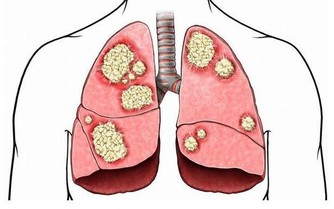

近年來癌症的發生逐漸年輕化,每年都有大量的年輕人被確診為癌症。很多腫瘤專科的大夫在臨床上深有體會,尤其是胃癌、肺癌、腸癌等常見癌症更是如此。

隨著科普保健,大家也都明白癌症的發生不是單一的因素導致的,可能與各個方面都有關係,比如過分的勞累、生活作息不規律等。